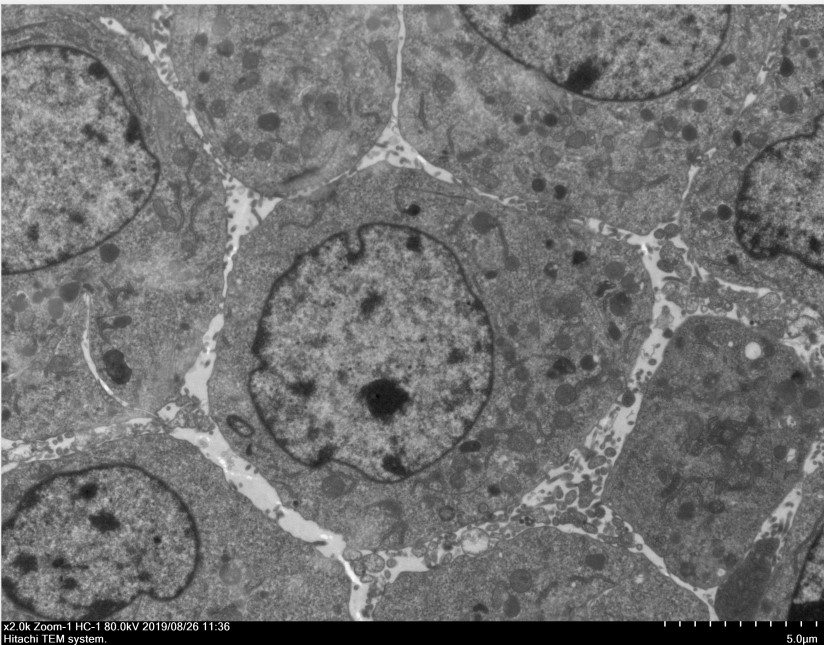

四、成果展示

透射電鏡,即透射電子顯微鏡(TEM),電子束在穿過(guò)樣品時(shí),會(huì)和樣品中的原子發(fā)生散射,樣品上某一點(diǎn)同時(shí)穿過(guò)的電子方向是不同,這樣品上的這一點(diǎn)在物鏡1-2倍焦距之間,這些電子通過(guò)過(guò)物鏡放大后重新匯聚,形成該點(diǎn)一個(gè)放大的實(shí)像,可以看到在光學(xué)顯微鏡下無(wú)法看清的小于0.2um的超微結(jié)構(gòu),主要應(yīng)用于物質(zhì)內(nèi)部的超微結(jié)構(gòu)觀察。